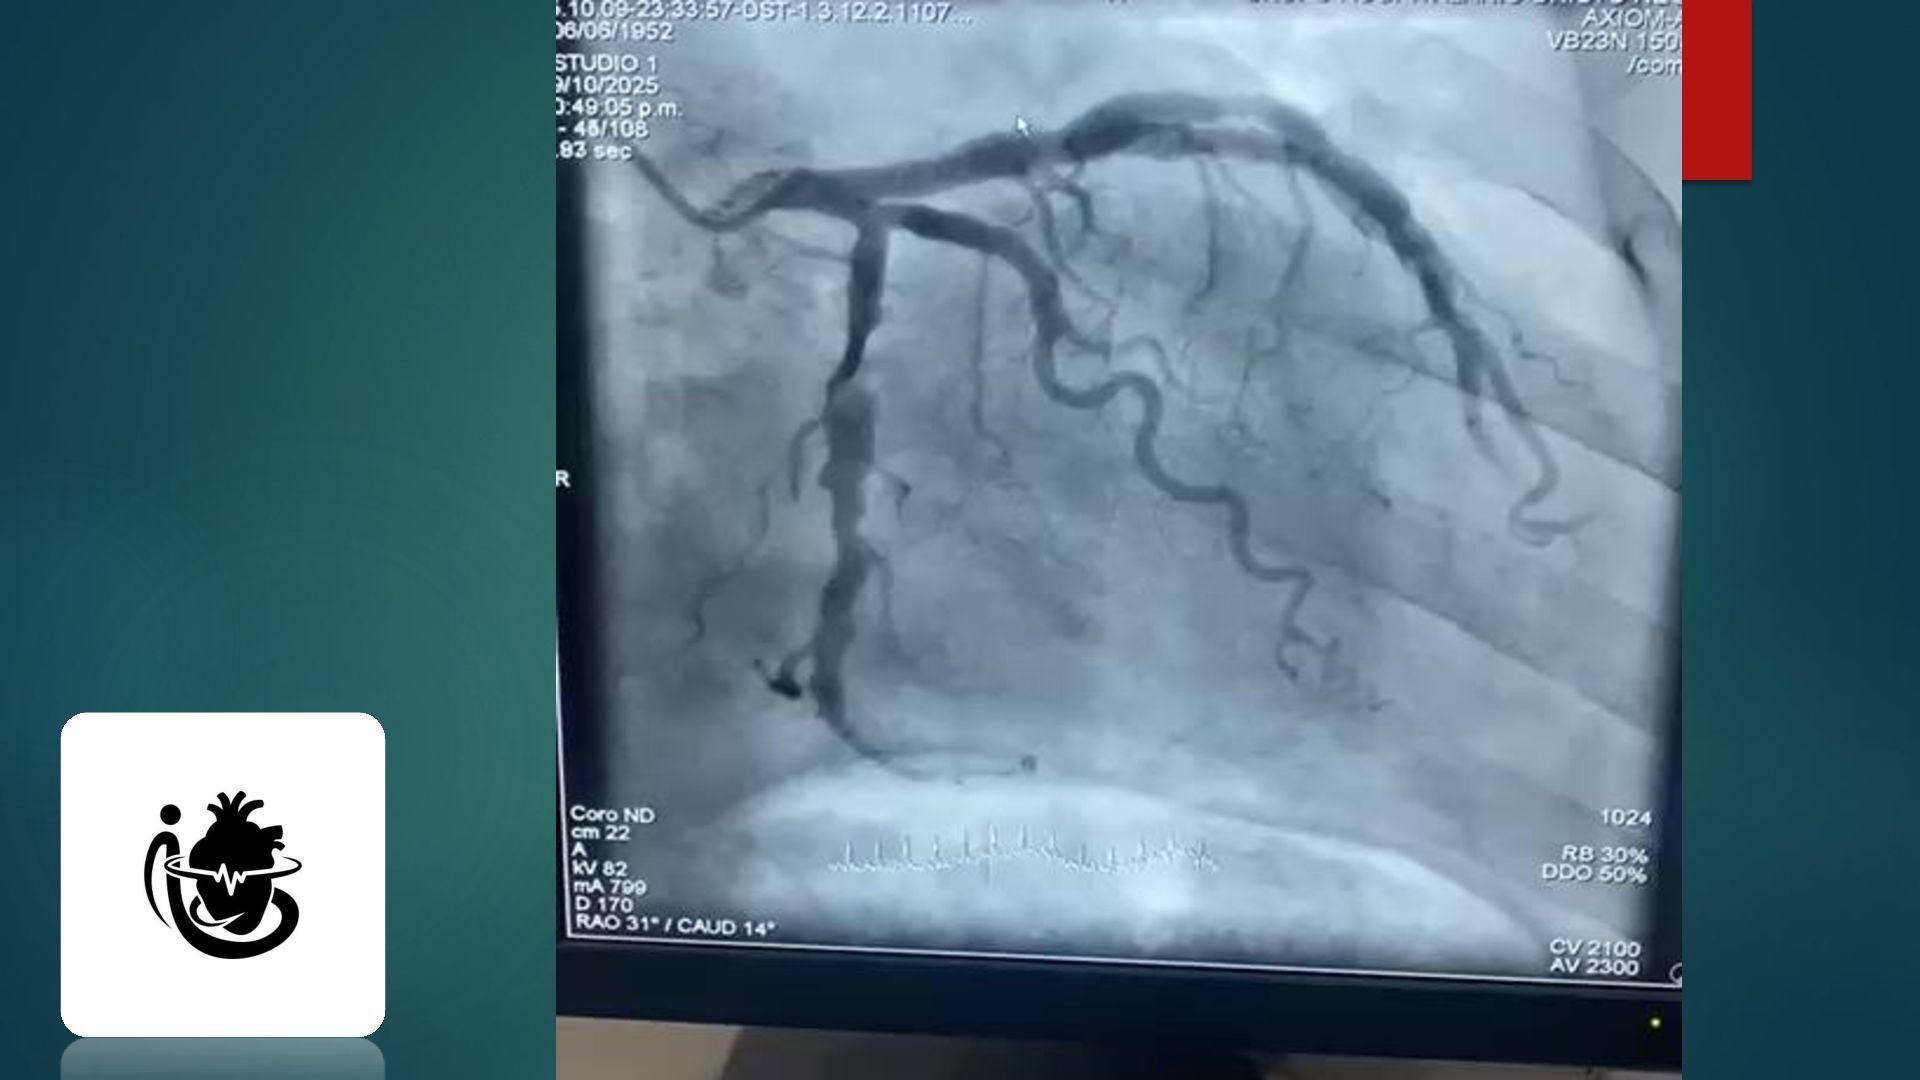

o g a c a r d i o v a s c u l a r ANATOMÍA Y FISIOLOGÍA CARDIOVASCULAR D r a . I s a m a r G . C h a v a r r i a B e r n a r d i n o